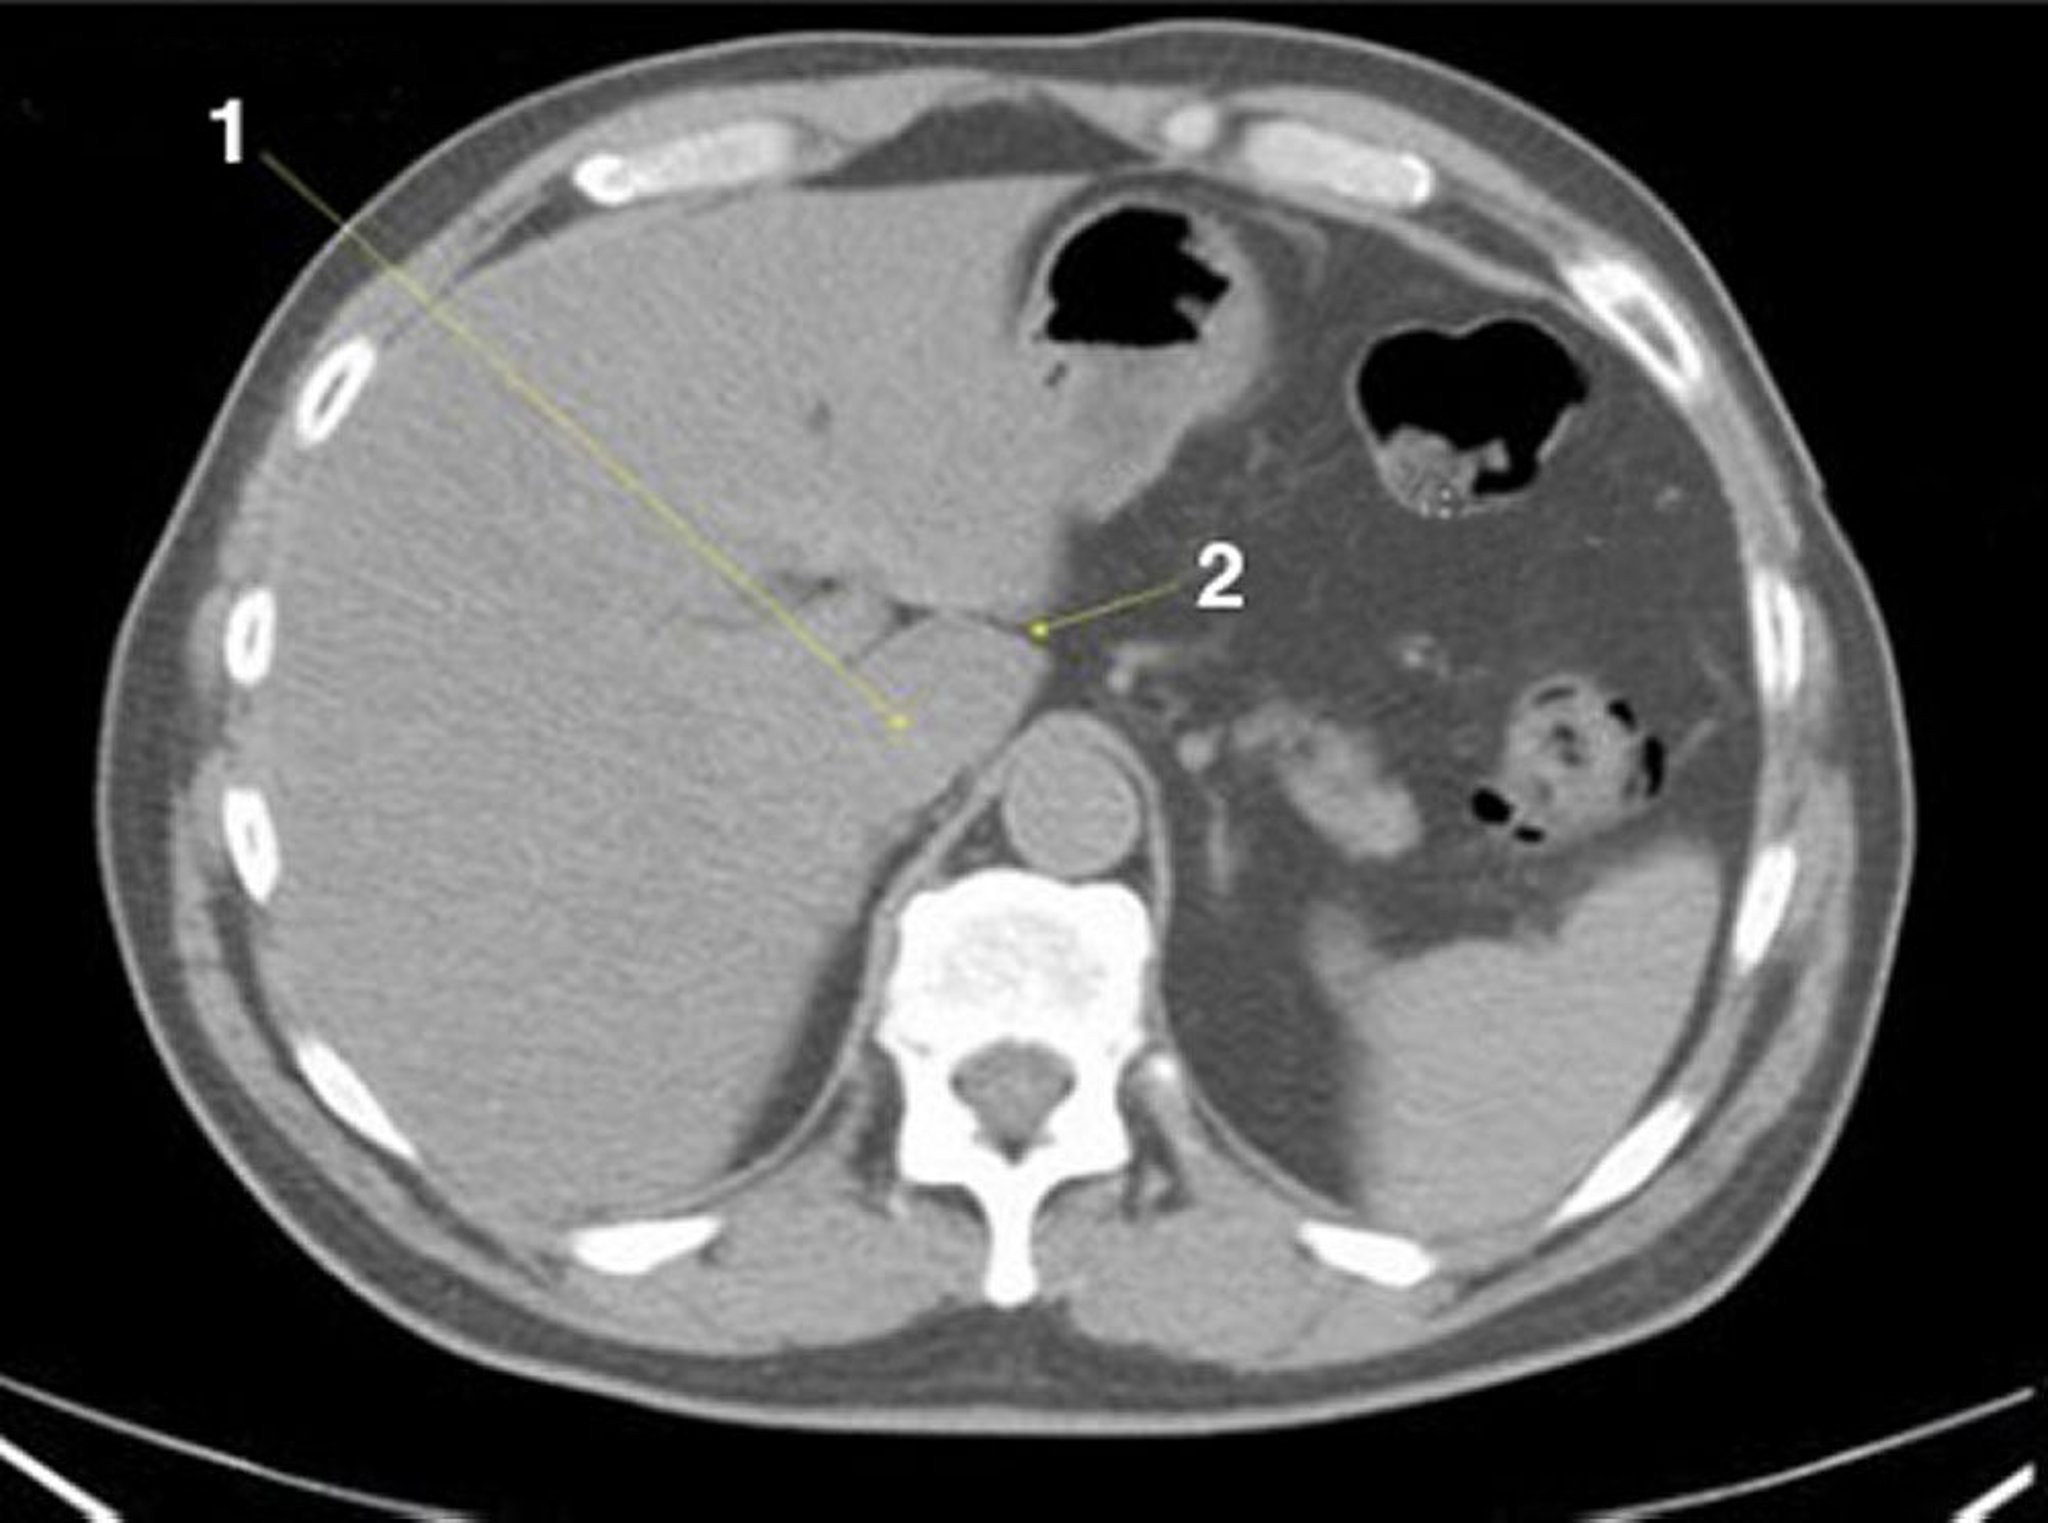

КТ брюшной полости и таза без контраста, демонстрирующая нормальную анатомию (слайд 4)

1 = хвостатая доля; 2 = щель венозной связки.